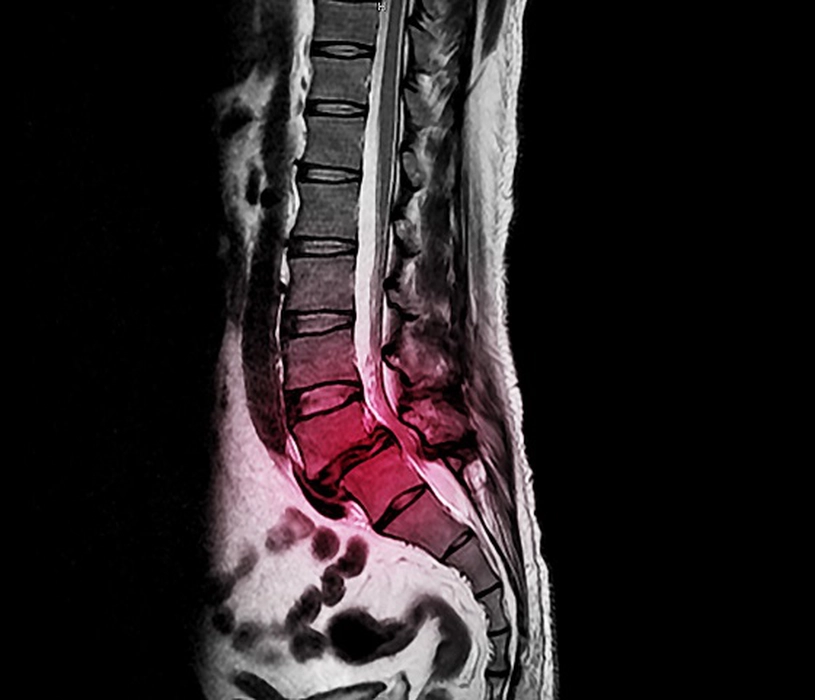

Sindromul coadă de cal. Afecțiunea cu care se confruntă sute de români